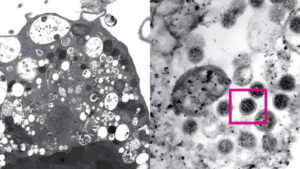

6、奥米克戎新变种XBB.1.5在美国迅速蔓延

美国疾病控制和预防中心(CDC)最新数据显示,截至去年12月25日至12月31日的一周内,XBB.1.5预计占美国新冠病例的40.5%,比前一周的21.7%几乎翻了一番。

美国明尼苏达大学传染病专家奥斯特霍姆表示,“目前全球所面临最糟糕的新冠变异株可能就是XBB.1.5。”